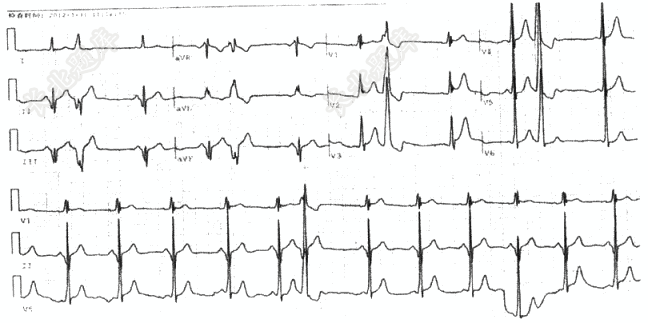

- 单项选择题请选出正确诊断( )

A、窦性心律,偶发室早,B型预激

B、窦性心律,陈旧性下壁心梗,偶发室早

C、窦性心律,偶发室早,A型预激

D、窦性心律,频发室早,A型预激

E、窦性心律,频发室早,B型预激